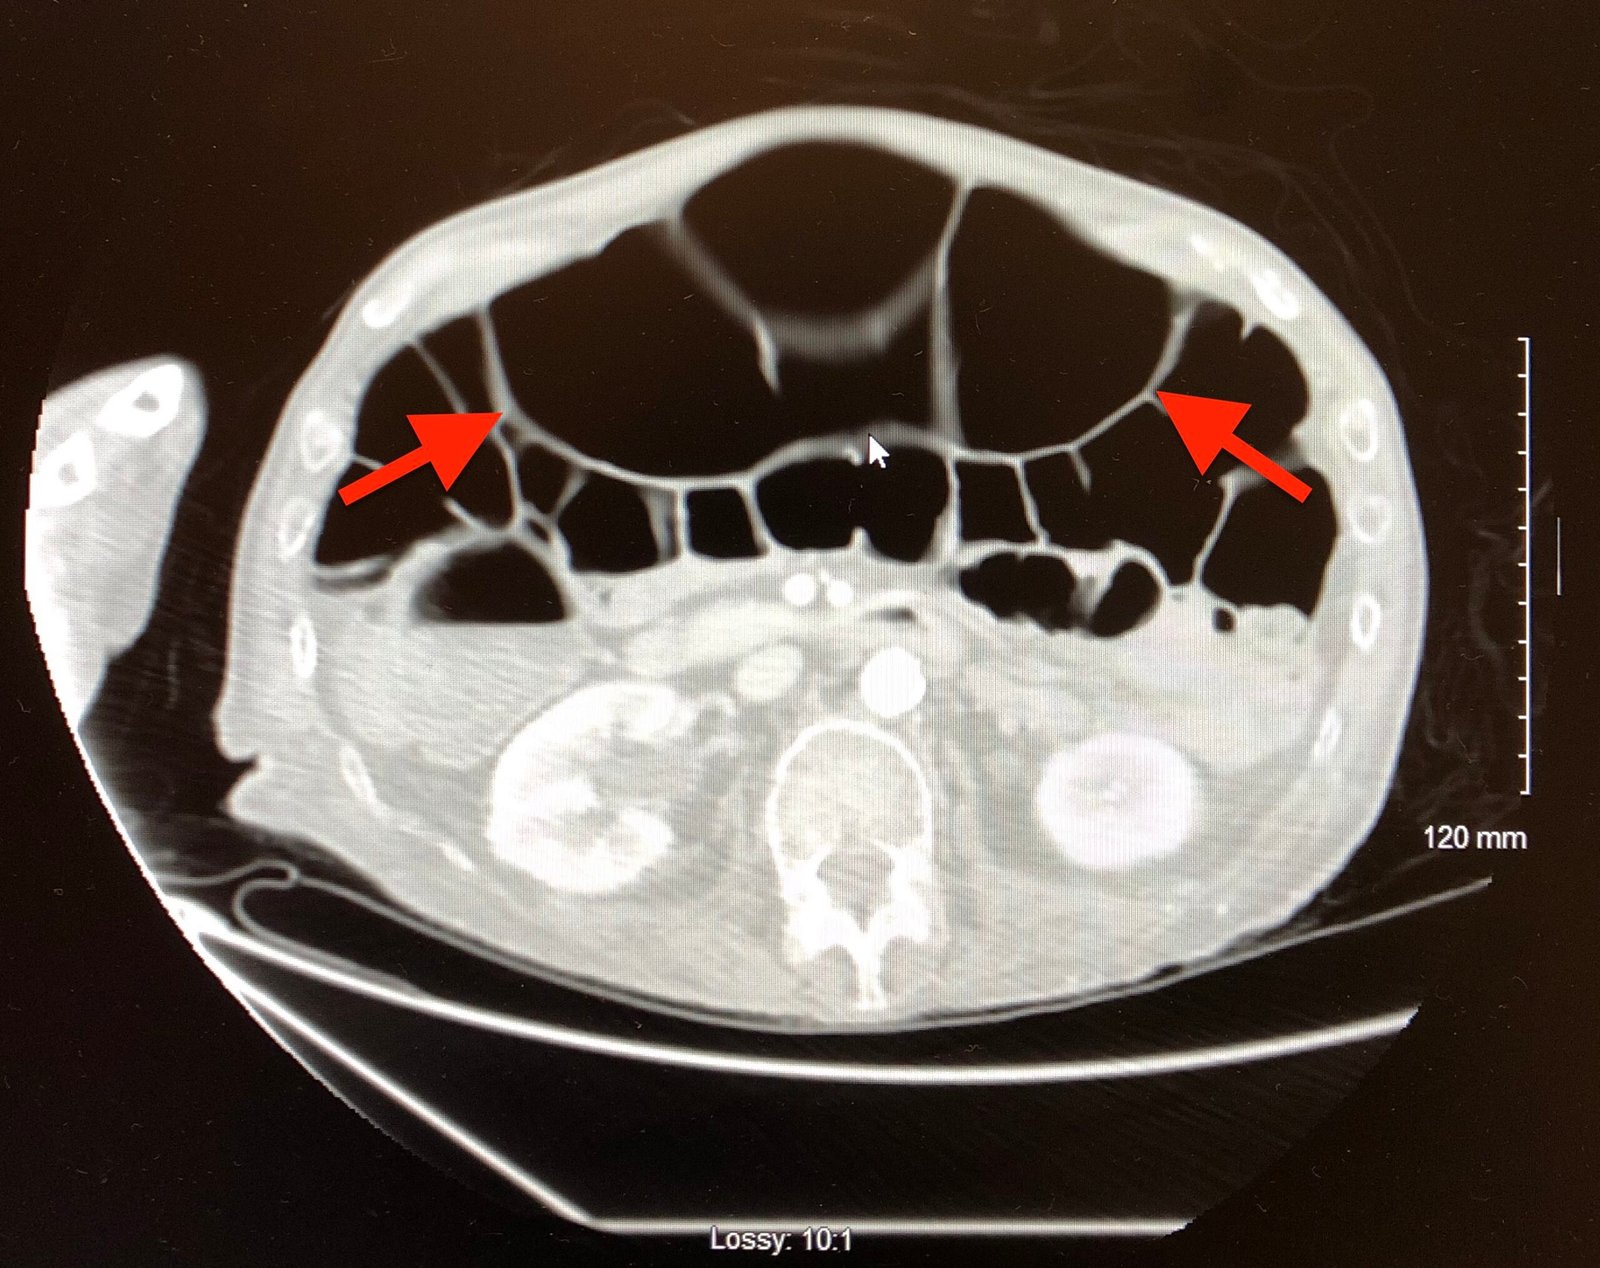

A Case Report of Ogilvie’s Syndrome in a 58-year-old Quadriplegic

Ogilvie’s syndrome (acute colonic pseudo-obstruction) is a rare disorder characterized by an acute dilation of the colon measuring greater than 10 centimeters. Common symptoms associated with Ogilvie’s include abdominal distension, abdominal pain, nausea, vomiting, constipation, and diarrhea. This report presents an uncommon case of a quadriplegic presenting to the emergency department with complaints of abdominal distention. Computed tomography and radiographic imaging studies were consistent with Ogilvie’s syndrome. The patient was admitted to the hospital and started on stool softeners and bowel rest with resolution of symptoms.

Ogilvie’s syndrome, quadriplegic, abdominal distension, colonic pseudo-obstruction.